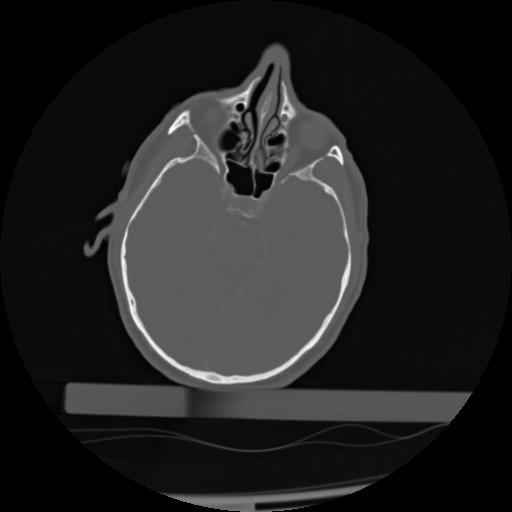

21 ANGIO,CE,Axial,3.0,ANGIO,,